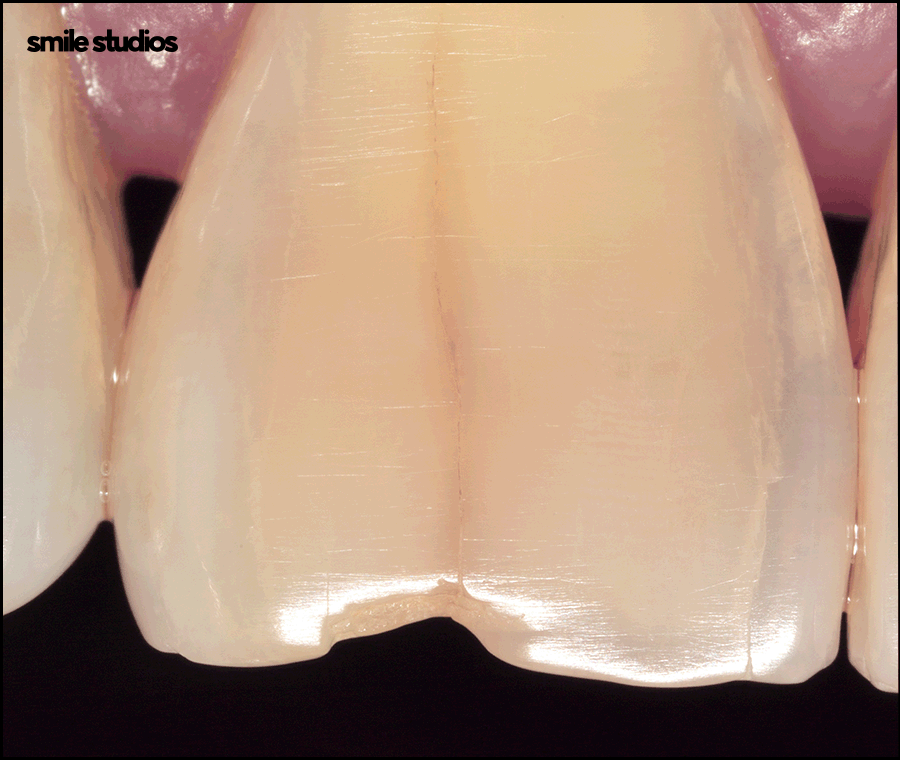

손상된 치아 앞면을 얇게 다듬거나 혹은 삭제하지 않고 세라믹 재질의 보철물을 제작해 부착하는 방식입니다.

심미적으로 문제가 되는 부분을 감추면서 모양, 색상을 개선할 수 있는 비침습적 심미치료입니다.

세라믹 재질은 기존 자연치와 구별되지 않을 만큼 투명도, 색감이 뛰어나다는 특징이 있습니다.

금이 생긴 영구치도 이 방법을 통해 새 것처럼 복원할 수 있습니다.